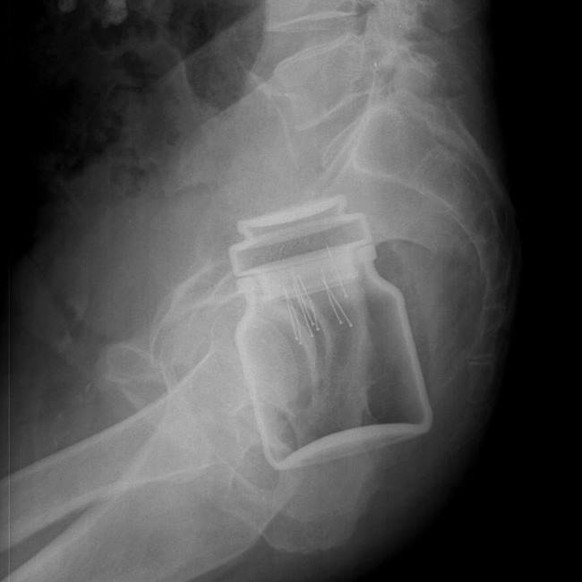

Zementeinlauf – oder: Wenn der Anus zur Sackgasse wird

Ein homosexuelles Pärchen hatte einen genialen Einfall: Warum sich nicht ein bisschen flüssigen Zement in den Anus kippen? Für dieses waghalsige Unterfangen wird nur ein Trichter benötigt.

Wie das von Zement naturgemäss erwartet wird, wurde dieser irgendwann hart. Der so entstandene Zementblock musste operativ entfernt werden. Die beiden liessen ihre Händchen während des Eingriffes nicht los.